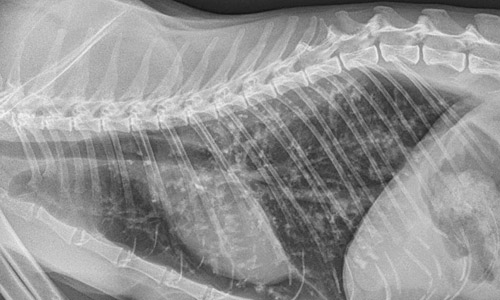

В ветеринарной практике разработан спектр тестов, чтобы получить результаты в день обращения. Ветеринар назначает рентгеновский снимок, рекомендует процедуру бронхоальвеолярного лаважа (БАЛ), которая позволяет собрать образцы клеток и жидкости из лёгких кошки для лабораторного анализа. При осмотре бронхиальных труб используют эндоскоп.